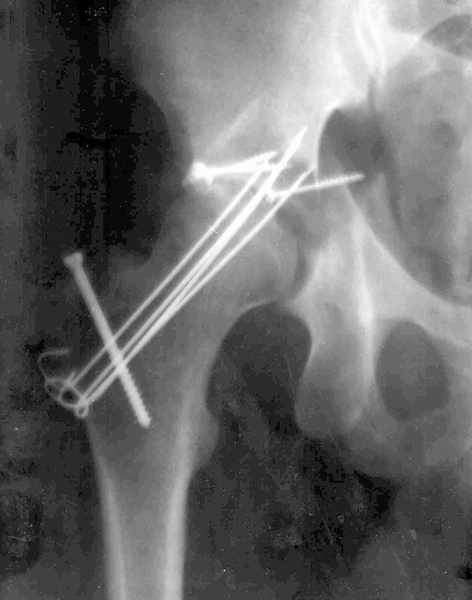

Мужчина 32 года, автотравма 6 недель назад. При поступлении был установлен диагноз "Ацетабулярный перелом". Вывих бедра не был установлен.

После установления вывиха бедра через 3 недели после травмы больному выполнена попытка открытой репозиции, остеосинтез вертлюжной впадины, Бедро фииксировано трансартикулярно спицами. После операции неврит седалищного нерва. В течение ещё 3-х недель после операции установлено что отломки не репонированы, вывих бедра не устранён (см. КТ и рентгенограмму), неврологической динамики нет. Возние вопрос о повторном оперативном вмешательстве по поводу чего разгорелись жаркие споры и сформировалось следующие мнения:1. Тотальное эндопротезирование с цементной фиксацией чашки протезом "ЭСИ" (другого протеза нет)2. Повторная открытая репозиция бедра с замещением дефектов вертлюжной впадины аутокостью с целью подготовки для последующего эндопротезирование. Предполагается фиксация тазобедренного сустава в послеоперационном периоде гипсовой повязкой или аппаратом внешней фиксации.Прошу высказать ваше мнение о тактике дальнейшего лечения пациента, о предложенных вариантах. Отдельный вопрос о возможности первичного тотального эндопротезирования при ацетабулярных переломах. (Лечащий врач настаивал перед первой операцией на выполнении тотального эндопротезирование с цементной фиксацией чашки через 3 недели после травмы)

Было бы существенным посмотреть обзорную R-грамму до операции. По данным послеоперационных снимков и КТ имеется низкий двухколонный перелом или

высокий Т-образный перелом с отрывом свода. Для уточнения необходиы косые проекции (Judet). Весь ли седалищный нерв молчит или только м/б порция?

Высылаю прямой обзорный и косой подвзошный снимки, косой запирательный неудовлетворительного качества.